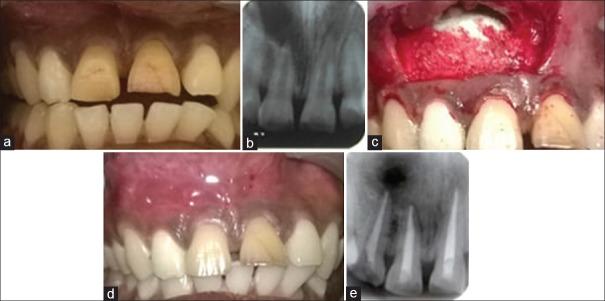

牛初乳在牙髓外科根尖周缺损中的应用:两例病例报告。

Use of bovine colostrum in periapical defects following surgical endodontics: Two case reports.

Periapical lesions are the most common pathological conditions involving teeth which often require surgical intervention. To achieve optimal healing both clinically and radiographically, bone grafts and barrier membranes have been used to fill the periapical defect after degranulation of the lesion. Colostrum is one of the new materials, which has osteoinductive or regenerative potential. The present case reports describe the use of bovine colostrum in the treatment of periapical inflammatory lesion with a follow-up period of 12 months. These case reports suggest that colostrum can be used to fill the periapical defect after degranulation, which has a favorable outcome.

摘要

根尖周病变是累及牙齿的最常见病理状况,通常需要手术干预。为了在临床和影像学上实现最佳愈合,在病变去肉芽后已使用骨移植和屏障膜来填充根尖周缺损。初乳是具有骨诱导或再生潜力的新材料之一。本病例报告描述了牛初乳在治疗根尖周炎性病变中的应用,随访期为12个月。这些病例报告表明,初乳可用于病变去肉芽后填充根尖周缺损,效果良好。